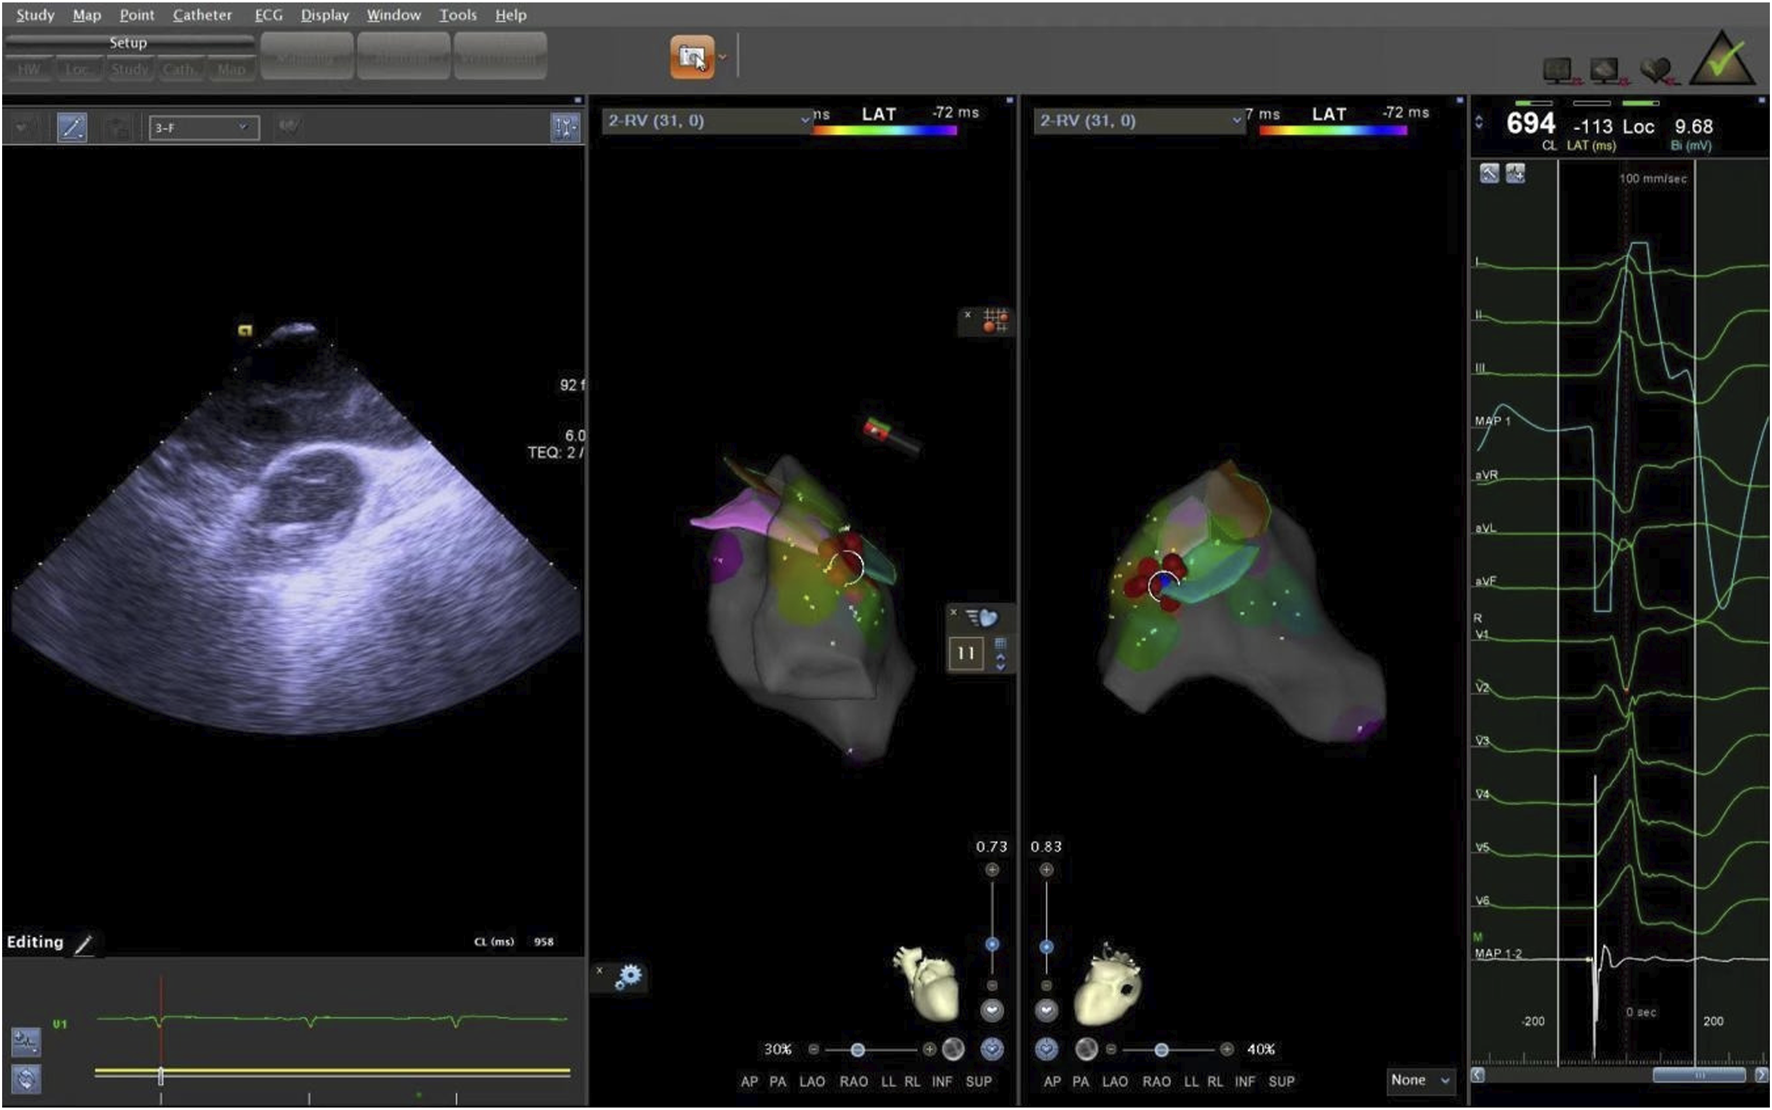

The supra-pulmonary sinus position is located above the pulmonary sinus junction plane. The infra-pulmonary sinus position includes locations at or below the pulmonary sinus junction plane, extending within 10 mm from the sinus floor (Acosta et al., 2015). After identifying the ablation target, radiofrequency ablation was performed with preset parameters of 43°C and 30W. The effectiveness of energy delivery (Dragasis et al., 2022) was validated by the disappearance of PVCs during ablation, and the duration of effective ablation was documented. The success criteria were defined as follows: 1) Complete elimination of PVCs on electroanatomic mapping; 2) Absence of preoperative-type premature contractions for 20–30 min after isoproterenol provocation. During the procedure, the CARTO3 three-dimensional anatomical mapping system and ICE were used to record the time, amplitude, and duration of bipolar potentials at the earliest activation site, in relation to the onset of the QRS complex on the surface electrocardiogram. We measured the distance from the effective ablation sites to the pulmonary artery sinus floor. After the procedure, we used ICE again to locate the ablation points, confirming the precise locations of the ablation targets (Figures 7, 8).

Figure 7. The ablation target of junction of LPC and APC. LPC, Left pulmonary cusp; APC, Anterior pulmonary cusp.